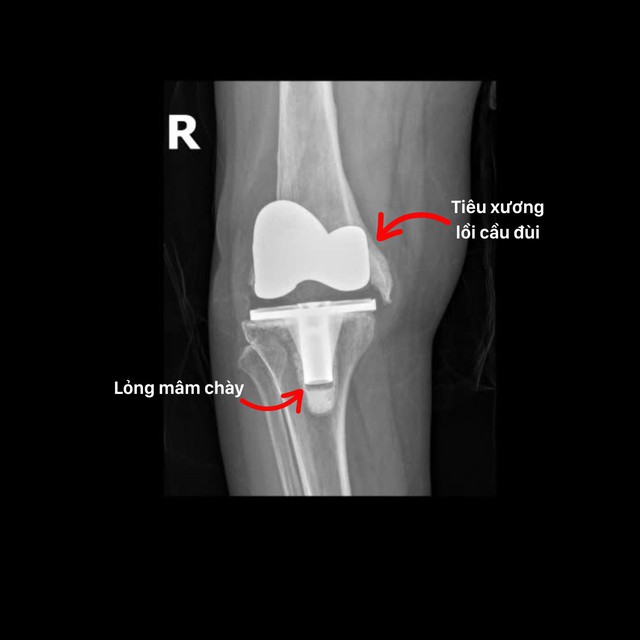

ຫວ່າງມໍ່ໆມານີ້, ທ່ານໝໍ, ທ່ານໝໍ ເຈືອງຊວນກວາງ ແລະ ຄະນະຜູ້ແທນຢູ່ໂຮງໝໍທົ່ວປະເທດ Hong Ngoc ປະສົບຜົນສຳເລັດໃນການຜ່າຕັດປ່ຽນຫົວເຂົ່າທີ່ສັບສົນໃຫ້ແກ່ຄົນເຈັບ NTT (ອາຍຸ 72 ປີ - Hung Yen ). ເມື່ອ 3 ປີກ່ອນ, ຄົນເຈັບໄດ້ປ່ຽນຫົວເຂົ່າຢູ່ໂຮງໝໍທ້ອງຖິ່ນ, ແຕ່ຍ້ອນການລະຄາຍເຄືອງຈາກຮ່າງກາຍ, ກະດູກໄດ້ຖືກທໍາລາຍເກືອບຫມົດ, ເຮັດໃຫ້ຂໍ້ກະດູກທຽມຂາດແລະ deviate ຈາກໂຄງສ້າງທາງກາຍະສາດ, ເຮັດໃຫ້ເກີດການໃຄ່ບວມ, ເຈັບ, ຂໍ້ຜິດປົກກະຕິ, ແລະການສູນເສຍການເຄື່ອນໄຫວ.

ອາການແຊກຊ້ອນຂອງ osteolysis condyle femoral ແລະ laxity ພູພຽງ tibial ຫຼັງຈາກການປ່ຽນຫົວເຂົ່າ.

" ນີ້ແມ່ນກໍລະນີທີ່ຫາຍາກເພາະວ່າຄົນເຈັບໄດ້ສູນເສຍ condyle femoral ຢ່າງສົມບູນ, ເຮັດໃຫ້ບໍ່ມີການສະຫນັບສະຫນູນການແກ້ໄຂຂໍ້ຕໍ່ຫົວເຂົ່າໃຫມ່, ທ່ານຫມໍຜ່າຕັດຕ້ອງປ່ຽນຂໍ້ກະດູກຫົວເຂົ່າແລະໃນເວລາດຽວກັນກໍ່ສ້າງ condyle femoral (ທ້າຍຕ່ໍາຂອງ femur) ເພື່ອສ້າງຄວາມຫມັ້ນຄົງແລະຊ່ວຍໃຫ້ການເຄື່ອນທີ່ຂອງຂໍ້ຕໍ່ມີຄວາມຍືດຫຍຸ່ນ .